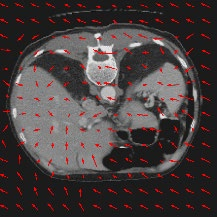

Transformers have made remarkable progress towards modeling long-range dependencies within the medical image analysis domain. However, current transformer-based models suffer from several disadvantages: (1) existing methods fail to capture the important features of the images due to the naive tokenization scheme; (2) the models suffer from information loss because they only consider single-scale feature representations; and (3) the segmentation label maps generated by the models are not accurate enough without considering rich semantic contexts and anatomical textures. In this work, we present CASTformer, a novel type of generative adversarial transformers, for 2D medical image segmentation. First, we take advantage of the pyramid structure to construct multi-scale representations and handle multi-scale variations. We then design a novel class-aware transformer module to better learn the discriminative regions of objects with semantic structures. Lastly, we utilize an adversarial training strategy that boosts segmentation accuracy and correspondingly allows a transformer-based discriminator to capture high-level semantically correlated contents and low-level anatomical features. Our experiments demonstrate that CASTformer dramatically outperforms previous state-of-the-art transformer-based approaches on three benchmarks, obtaining 2.54%-5.88% absolute improvements in Dice over previous models. Further qualitative experiments provide a more detailed picture of the model's inner workings, shed light on the challenges in improved transparency, and demonstrate that transfer learning can greatly improve performance and reduce the size of medical image datasets in training, making CASTformer a strong starting point for downstream medical image analysis tasks.